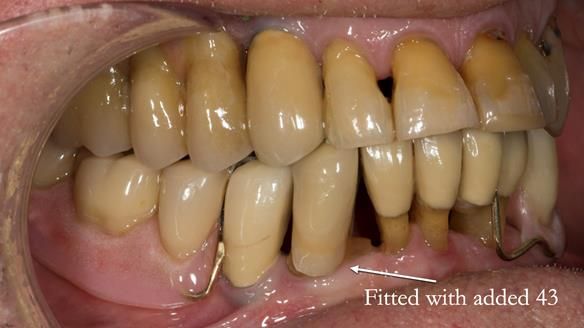

In 2022, tooth 43 fractured.

An artificial tooth was added to the RPD

by welding a cobalt–chrome tag to the bar

and adding the tooth.

The denture continued to function extremely well.